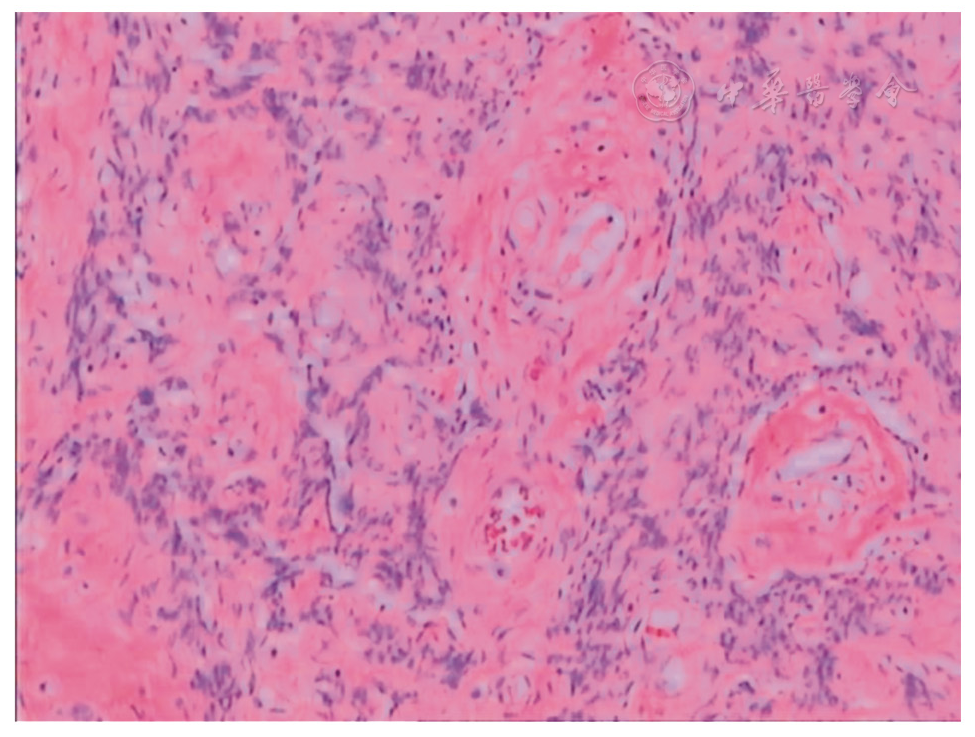

图1 普通子宫平滑肌瘤

图2 血管性平滑肌瘤

图3 子宫静脉内平滑肌瘤

图4 伴出血的平滑肌瘤

图5 间质细胞肉瘤